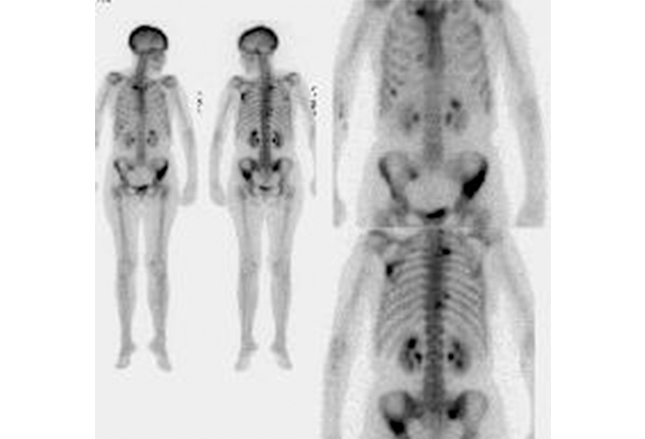

SCLC常见骨转移。上图为SCLC患者正面及背面全身骨扫描。脊柱、肋骨、左肩胛骨和骨盆均可见放射性示踪剂摄取,提示骨转移。